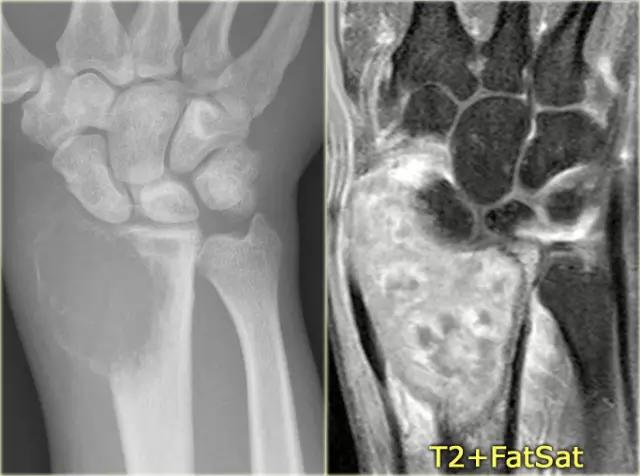

在左图,桡骨的一个骨巨细胞瘤具有不明确的边缘,破坏软骨下骨板和向软组织延伸。在右图,在胫骨近端的巨细胞瘤具有稍微更好的限定的边缘和非中断的皮质骨。

注意侵袭性外观与不明确的边界,延伸到软组织和软骨下骨板的破坏。

在骨骺和干骺端的定位有利于GCT的诊断。在右侧冠状T1加权CE图像。

有弥漫性不均匀强化,并延伸至腕关节和骨和软组织周围水肿。

同一病人在刮除和水泥放置后的随访期间。存在与骨水泥相邻的骨的骨溶解的软组织肿胀。这表明复发或残留病变。